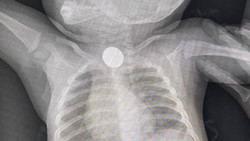

Ошто 9 жашар баланын өпкөсүнөн мистенин кабыгы операциясыз алынды

Чоң-Алайда 8 айлык баланын кызыл өңгөчүнөн тыйынды операциясыз алып чыгышты.

Сүрөт

Ошто 13 жаштагы баланын өпкөсүнөн ышкырык операциясыз алынды. Сүрөт